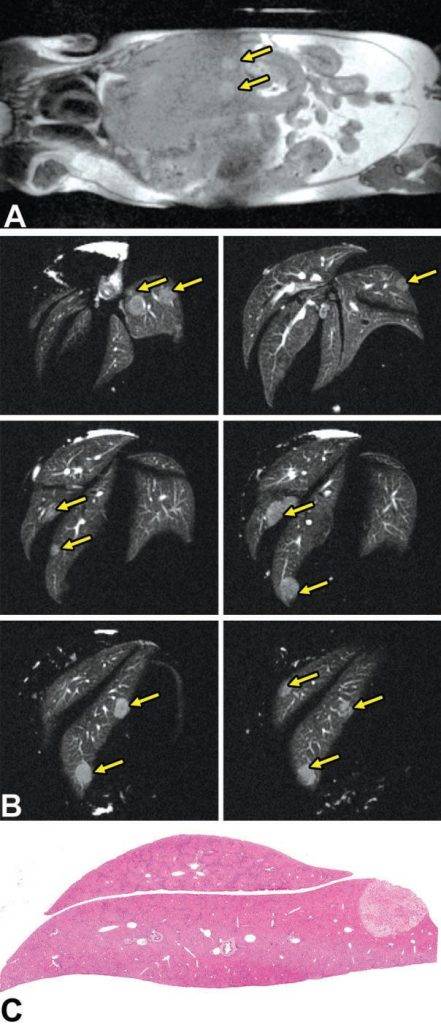

活体磁共振成像在模型小鼠中检测到局灶性肝损伤(图A)。肝脏的高分辨率离体MRH评估可以在小鼠(图B和C)中鉴定几个单独的局灶性脂肪病变。通过常规组织病理学证实病变为局灶性脂肪改变(图C)。